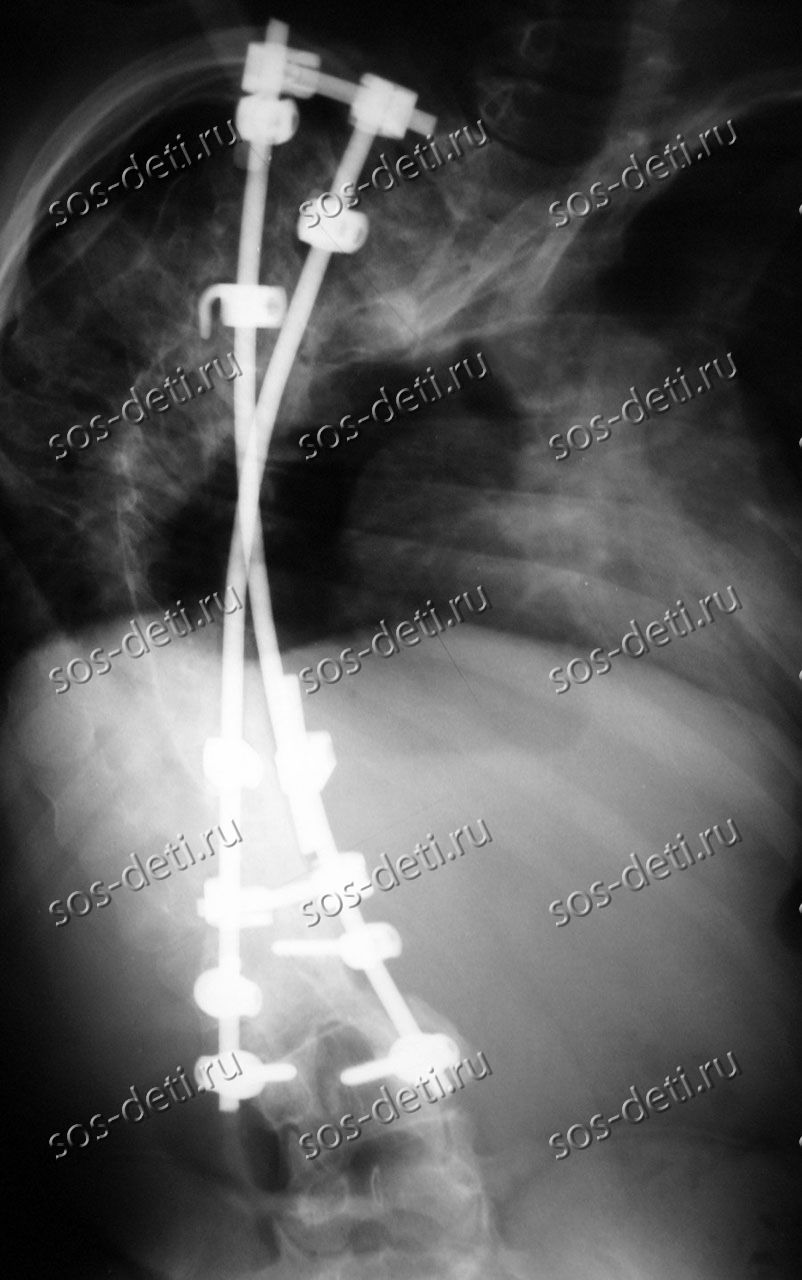

Ивану 15 лет, он из г. Сосенский Калужской области. Его диагноз – синдром Элерса-Данло, правосторонний грудопоясничный сколиоз 4 степени, реберный горб, состояние после оперативного лечения. В Государственном бюджетном учреждении здравоохранения «Калужская областная детская больница» ему по медицинским показаниям планируют установить имплантаты стабилизации позвоночника Medtronic (США). Оплата имплантатов за счет бюджетных средств не производится. Стоимость базовой комплектации имплантатов и расходных материалов составляет 703 840 рублей.

Иван – ребенок-инвалид, проживает в приемной семье вместе с младшей сестрой. Среднедушевой доход в семье составляет 16 150 рублей. Доходы семьи складываются из пособий на воспитание и содержание приемных детей. Мама – Беляева Людмила Викторовна не работает, поскольку приемные дети находятся на домашнем обучении и нуждаются в постоянной заботе. При финансовой поддержке фонда «Милосердие – детям» в 2013 году Ивану была проведена первичная коррекция деформации позвоночника имплантами Medtronic (США). За 3 года мальчик вырос и имплантаты необходимо заменить на больший размер. По информации лечащего врача эта операция должна стать завершающим этапом в лечении Ивана.

За плечами Ивана уже стоит одна операция, он благополучно справился с ней 4 года назад. Тогда мальчик начал сильно хромать, ребро буквально ушло в противоположную сторону. Но после первой операции уже был значительный результат – горб уменьшился на 40 градусов.

Первую операцию сделали раньше времени, потому что позвоночник начало скручивать по спирали, Ваня сам маленький, а горб был уже слишком большой. Операция была жизненно необходимой, без операции Ивана могло полностью парализовать, или мог бы просто умереть. Но первая операция прошла хорошо. За 4 года Иван сильно вырос, имплантаты нужно менять на больший размер. Предстоит вторая - завершающая операция и снова при финансовой поддержке фонда «Милосердие – детям».